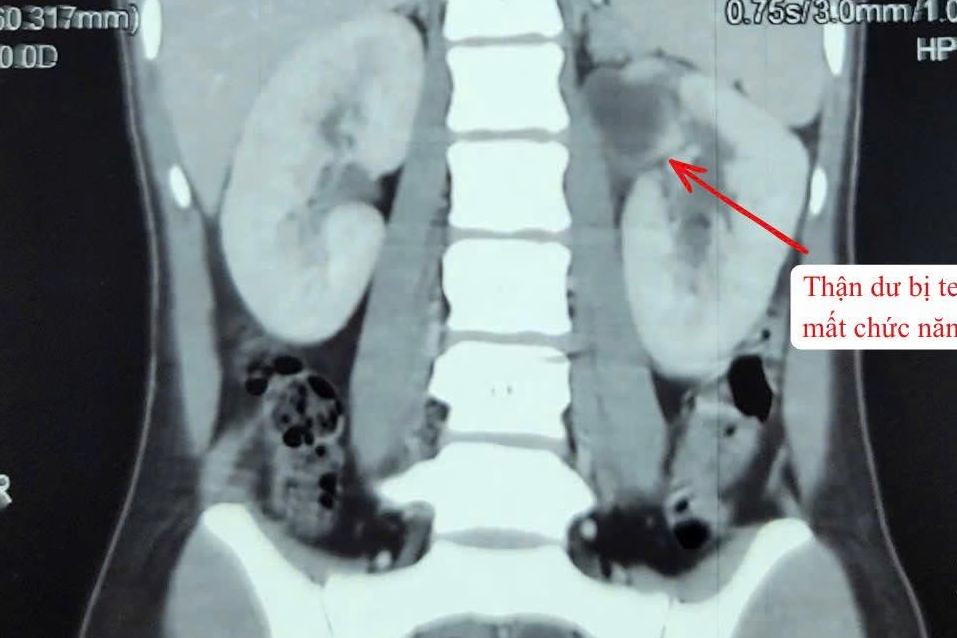

Hiếm gặp cô gái có 3 quả thận

Theo các bác sĩ, những trường hợp có 3 quả thận chỉ chiếm 1% dân số. Bệnh có thể gây nhiễm trùng tiết niệu tái phát, tiểu buốt, tiểu rắt, đau vùng hông lưng.